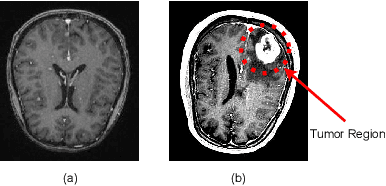

Abstract:Distinguishing normal from malignant and determining the tumor type are critical components of brain tumor diagnosis. Two different kinds of dataset are investigated using state-of-the-art CNN models in this research work. One dataset(binary) has images of normal and tumor types, while another(multi-class) provides all images of tumors classified as glioma, meningioma, or pituitary. The experiments were conducted in these dataset with transfer learning from pre-trained weights from ImageNet as well as initializing the weights randomly. The experimental environment is equivalent for all models in this study in order to make a fair comparison. For both of the dataset, the validation set are same for all the models where train data is 60% while the rest is 40% for validation. With the proposed techniques in this research, the EfficientNet-B5 architecture outperforms all the state-of-the-art models in the binary-classification dataset with the accuracy of 99.75% and 98.61% accuracy for the multi-class dataset. This research also demonstrates the behaviour of convergence of validation loss in different weight initialization techniques.